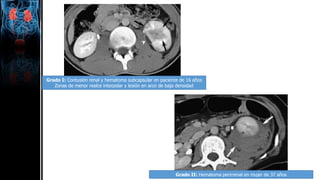

Grado I: Contusión renal y hematoma subcapsular en paciente de 16 años

Zonas de menor realce interpolar y lesión en arco de baja densidad

Grado II: Hematoma perirrenal en mujer de 37 años

Grado III: Laceración cortical en hombre de 61 años por traumatismo contuso

Grado IV: Infarto segmentario en hombre de 34 años tras traumatismo contuso

Zona cuneiforme delimitada en regio interpolar

Grado IV: Laceracion de sistema colector en mujer de 43 años por traumatismo contuso

Fuga de contraste por laceración y hematoma perirrenal